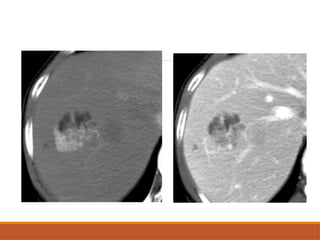

On CT scan

CECT - Discontinuous, nodular, peripheral

enhancement starting at arterial phase & gradual

central filling in.

Retention of contrast in delayed phase.

Enhancement must match blood pool in each

phase(similar to aorta in arterial phase , portal vein in

portal venous phase).

On CT scan CECT- Discontinuous, nodular, peripheral enhancement starting at arterial phase & gradual central filling in. Retention of contrast in delayed phase. Enhancement must match blood pool in each phase(similar to aorta in arterial phase , portal vein in portal venous phase).

• #12 Grey scale usg image showing well defined hyperecheic lesion in segment 6 of right lobe Axial cect image in portal veous phase showing giant hemangioma in left lobe of liver with peripheral nodular enhamncement

• #31 Axial cect images of hcc in segment 4a in showing enhancement odf elsion in arterial phase and washout of tumour in portal venous phase and delayed phases So early washout of the contrast suggestive of hcc